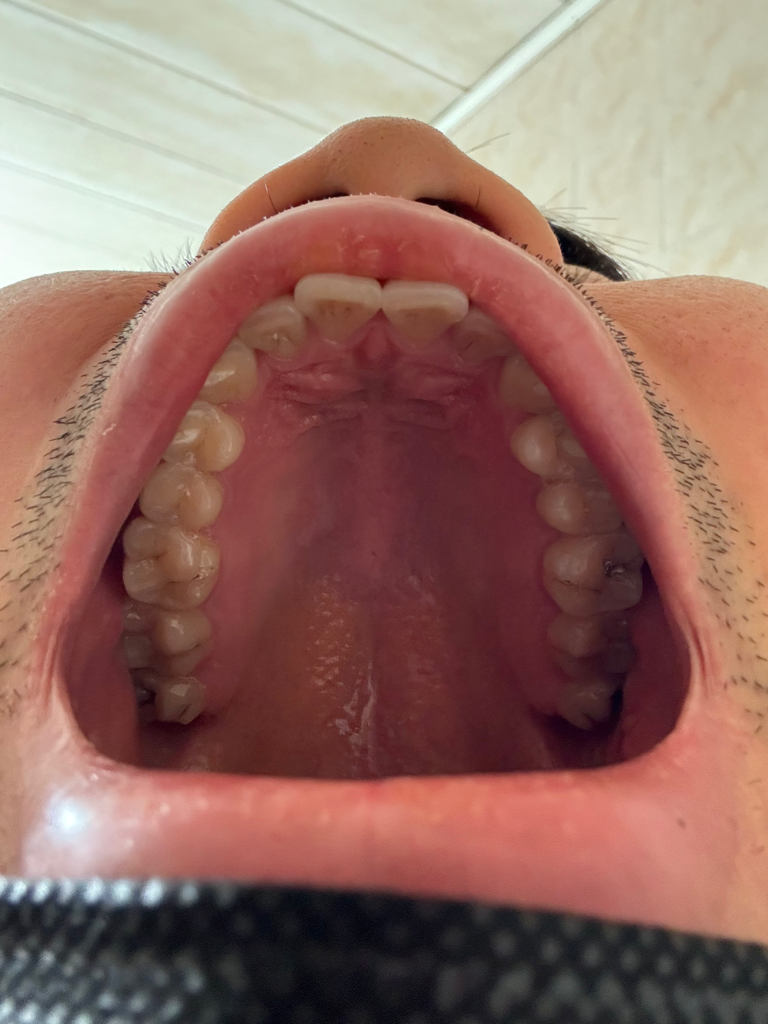

특별하게 이상이 있는 것처럼 보이지는 않습니다

너무 걱정하지 않으셔도 되겠습니다

입 사진에 특별한 이상은 없어서 구강암 가능성은 없을 것으로 판단됩니다. 점막이 약간 까진 것 같은데 자극적이거나 딱딱한 음식만 당분간 피해 보시기 바랍니다.